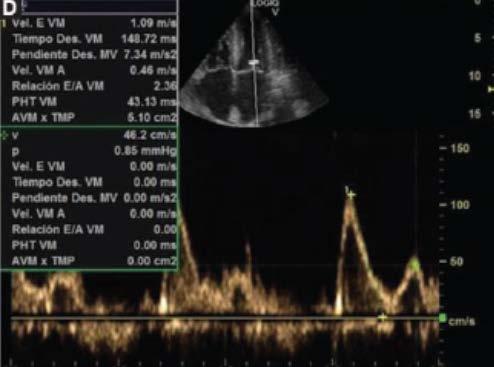

1. Evoluciona con clínica tórpida, desarrollando signos de IC por lo que se solicita electrocardiograma (Fig. 1), ecocardiograma Doppler color (Fig. 2) y resonancia magnética nuclear cardiaca. Esta última informa: ventrículo izquierdo no dilatado, leve incremento de espesor parietal septal (12 mm), fracción de eyección de ventrículo izquierdo: 51%. IM leve, AI moderadamente dilatada. Fibrosis difusa transmural inferoseptal basal e inferoseptal medial, fibrosis subendocárdica en pared inferior de ventrículo derecho. Valores de T1 mapping nativo aumentados en forma difusa (valores mayores a 1110 ms). Volumen extracelular (VEC) 55%, hallazgos compatibles con AC. Por referir palpitaciones se solicita estudio holter de 24 horas (Fig. 3).

Se diagnostica mieloma múltiple y AC con IC función sistólica preservada, iniciando tratamiento dirigido a ambas enfermedades. En su seguimiento presenta mejoría clínica de la función renal y cardiaca; luego de dos meses de tratamiento, las mediciones de NT-pro BNP y troponina I ultrasensible habían descendido un 30%. En ecocardiograma control se puede objetivar mejoría de la función diastólica, progresando desde una disfunción diastólica III (flujo transmitral tipo restrictivo) a una tipo I (flujo transmitral prolongado), mejoría en Doppler tisular y parámetros de deformación longitudinal global.

B

D

Figura 2. Ecocardiograma Doppler color. A: paraesternal 4 cámaras, hipertrofia concéntrica. B: deterioro de la función sistólica de ventrículo derecho evaluada por Doppler tisular. C: relación Doppler de flujo transmitral y Doppler tisular mitral lateral alterado. D: disfunción diastólica grado III. A

C

Ecocardiograma

Lo característico de esta enfermedad es que el infiltrado afecta aurículas y tabique interauricular, aumento simétrico del espesor parietal ventricular derecho e izquierdo con un aspecto brillante moteado tipo granular y sistema de conducción. Los cambios para comenzar a considerar el diagnóstico diferencial de AC son la relación Ee´ > 9.6, el volumen auricular izquierdo indexado y la disminución en la fracción de contractilidad miocárdica o fracción de acortamiento. Además, entre otros parámetros habituales pueden citarse el índice de excentricidad o espesor parietal relativo, ―ya que el fenotipo habitual en los pacientes con AC es de hipertrofia ventricular izquierda (HVI) concéntrica―, y el engrosamiento difuso valvar13.

Inicialmente, disminuye la complacencia auricular y aumenta la presión intraauricular, lo que lleva a que se ocupe menor tiempo tanto en el llenado ventricular como en el auricular. El descenso del llenado diastólico precoz es compensado por un enérgico llenado diastólico final, lo que, en estadios avanzados de la enfermedad, se traduce en una pseudonormalizacion del patrón. Por otro lado, otros autores han observado que la progresión de la enfermedad conlleva deterioro precoz de la diástole, pero no puede diferenciarse si este cambio se debe al envejecimiento normal celular. Es decir, que pueden observarse un patrón transmitral tipo pseudonormal, más habitual, o un patrón prolongado, el cual deberá diferenciarse de los cambios producidos por el envejecimiento. Otro aspecto a considerar es la afectación de la válvula mitral, ya que se ha observado una alta prevalencia de insuficiencia mitral que altera el patrón de llenado ventricular. Conforme avanza la enfermedad también se observan cambios en el patrón de las venas pulmonares. La evaluación de la función diastólica se correlaciona con la gravedad de la enfermedad y puede ser utilizada en su seguimiento14,15.